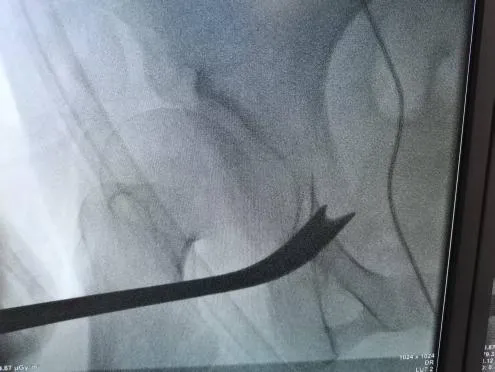

圖5-6:術(shù)中截骨